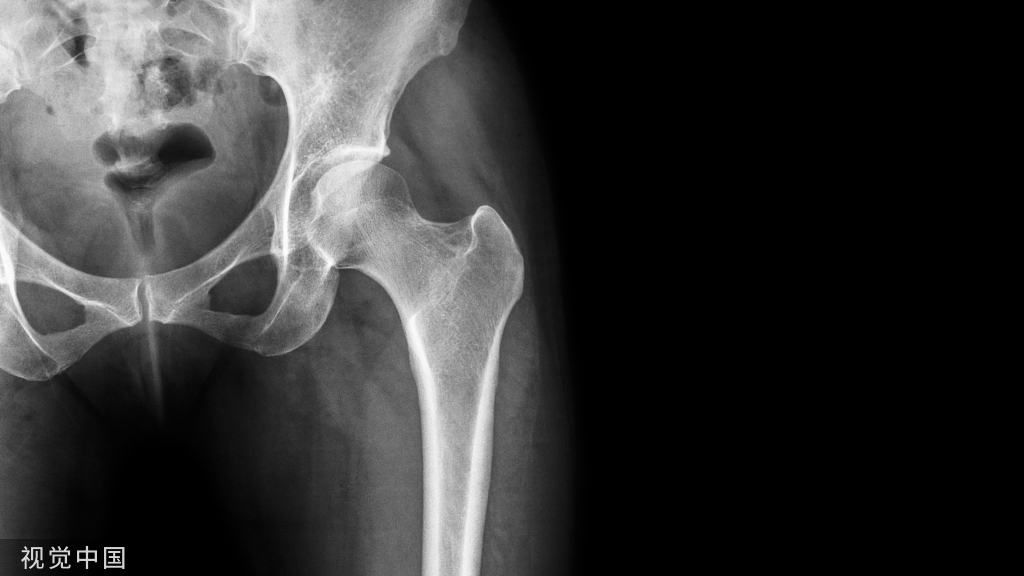

(三)下肢骨疾病中的应用

“偷梁换柱”的临床应用在下肢也较为常见。1965年,世界首例人工全股骨置换术用于治疗因佩吉特骨病导致的反复骨折患者。经过半个世纪的发展,人工全股骨置换术作为挽救性手术, 逐渐应用于因肿瘤、骨髓炎或创伤引起的巨大骨缺损的治疗,在保肢重建领域取得了突破进展(图4)

但是,全股骨置换术手术创伤大,手术适应证及术后康复标准仍不统一,而且研究多为个案报道,仍需大样本数据进一步研究。